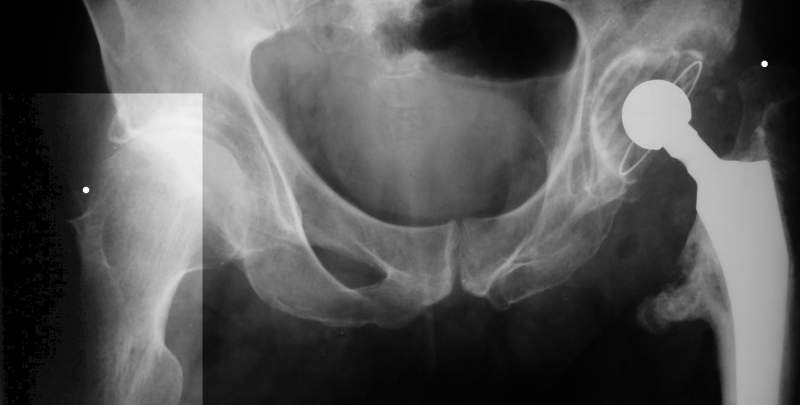

Насчет 8 см согласен с А.Н. Челноковым, это наверное ортопедическое за счет приводящей, сгибательной контрактуры и, возможно, колена. на ликвидацию укорочения у нас обычно уходит около 2-х нед. снимки в приложении, возможно не очень показательные, но других с ходу не нашел, завтра еще поищу.

Еще пара фото, ситуация несколько иная, задачи те же, открытое вправление застарелого вывиха в 2002, молодой возраст. Сейчас госпитализирована для эндопротезирования.

А за счет чего такое укорочение? По снимку не видно соответствующего дефекта. Ну плюс приводящая контрактура - но все равно как-то уж больно много. Может, сделать снимки и таза обзорный с обоими проксимальными отделами бедра, и коенный суставов с приложенной линейкой какой?

Судя по снимку, максимум истинное укорочение около 4 см, что может быть коррегировано интраоперационно. Вопрос в другом: куда ставить ацетабулярный компонент в истинную или во вновь сформированную ( впадина диспластичная).

Невозможно не согласиться с Анатолием, чтобы заниматься адекватным планированием как минимум прямая проекция таза должна быть сделана, как

максимум для оценки состояния мышц( насколько реально возможно низвести бедро) прямая проекция таза с тракцией за больную ногу.

The X ray that you provided does not show 8 cm of shortening. Perhaps you could send one showing the whole pelvis and proximal femurs.

I agree with Dr Eid's comments. The origin of the 8 cm leg length difference is a puzzle. Is this a clinical measurement? In that case contracture of the joint might affect the measurement. Can we see an AP pelvis to include both hip joints (including a calibration object with a known length) so that the difference in leg lengths that can be ascribed to the hip deformity and bony reabsorption can be measured. This sort of xray will help with templating for the TJR also. I would be very tempted to do a one stage procedure and accept some shortening. Shoe lifts should take care of a 3-4 cm difference.

До травмы проблем с ногой не было. Укорочения, болей и т.п. не отмечал. Сегодня перемерял укорочение - меньше 7 см намерять не

По уровню малых вертелов (с учетом рентгеновского увеличения) получается 5 см. Клинически ногу низвести путем тракции невозможно. Из движений - сгибание до 40*, остальные движения "символические".

Ортопедическое укорочение пострадавшей ноги может быть и 7, и 10 см. за счет контрактур в тазобедренном суставе, а вот истинное укорочение, судя по представленным рентгенограммам, вряд ли больше 4 см.